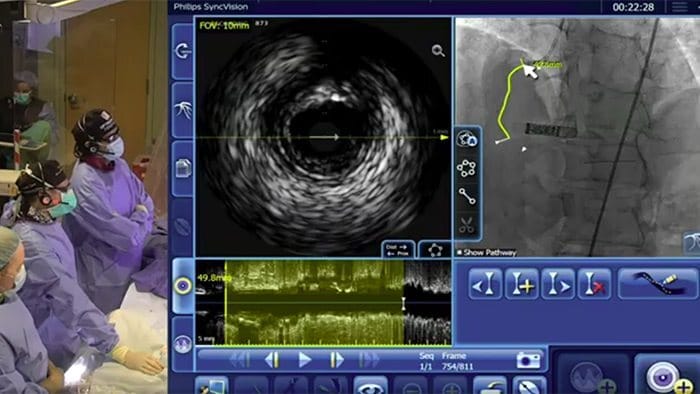

Asigne los valores de iFR directamente al angiograma, de modo que pueda ver con precisión qué partes de un vaso están produciendo la isquemia

Disponible en la nueva plataforma de aplicaciones intervencionistas Philips IntraSight y como actualización a los sistemas Core.

El Dr. Justin Davies explica cómo el corregistro de iFR puede identificar la localización de la enfermedad y el impacto probable de la ICP antes de aplicar el stent.

Presentación de la plataforma de todas las nuevas aplicaciones intervencionistas IntraSight de Philips, donde la adquisición de imágenes, la fisiología, el corregistro10 y el software se unen para facilitar la atención óptima del paciente. IntraSight ofrece un paquete integral de modalidades clínicamente comprobadas, como iFR/FFR, IVUS y corregistro10, para simplificar intervenciones complejas, acelerar procedimientos de rutina y proporcionar una mejor atención al paciente.

10. Herramientas de corregistro disponibles en la configuración de IntraSight 7 mediante SyncVision.